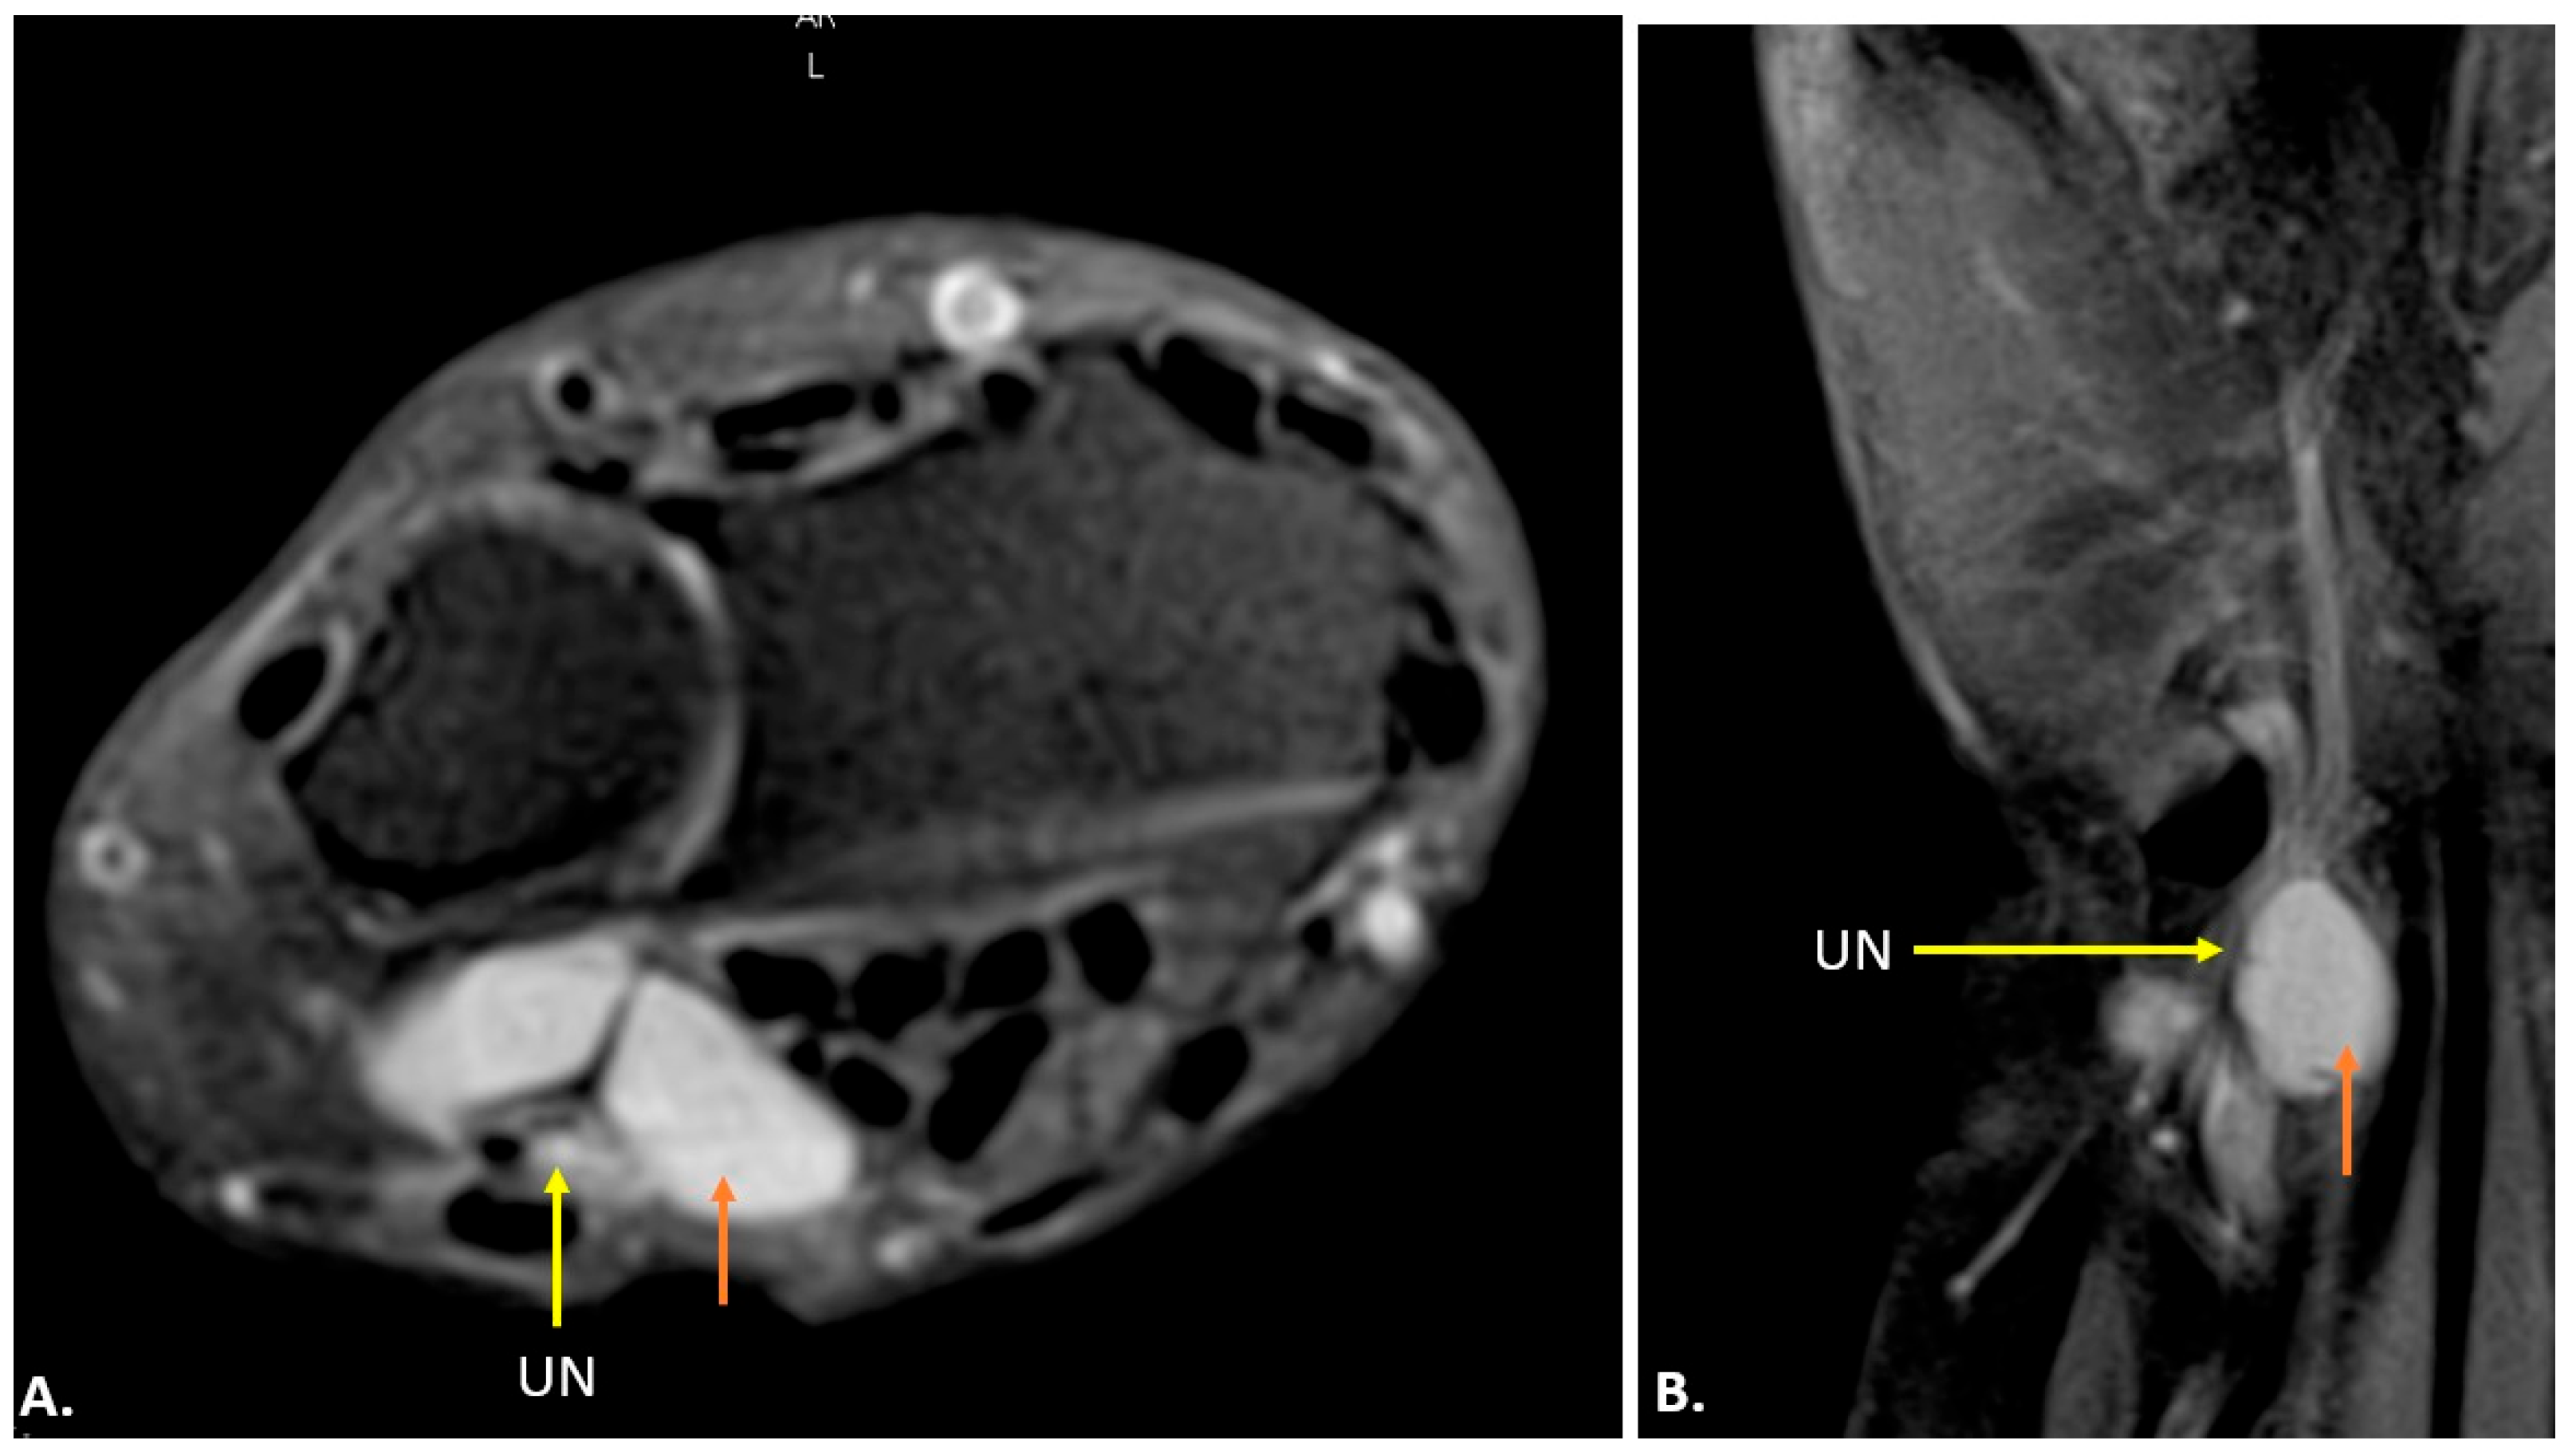

3.2. MRI Technique and Anatomy

| Idiopathic Ulnar Neuropathy | Ulnar nerve swelling/thickening with loss of normal fascicular pattern. No compressive lesion. | Increased T2 signal in the affected nerve segment, indicating oedema or inflammation. |